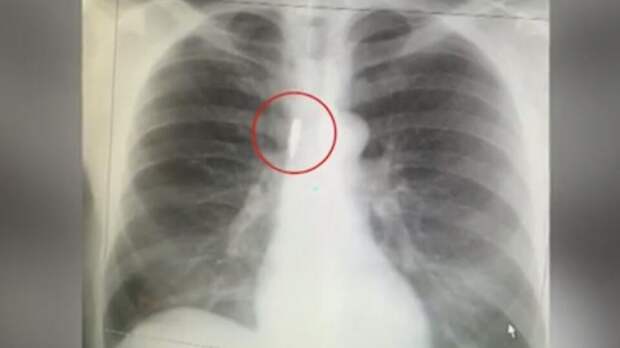

Чудесное спасение возможно: чудом выжил Дмитрий. На рентгеновском снимке – пуля, прошедшая в миллиметре от позвоночника. Когда террористы начали стрелять, Дмитрий стоял в очереди в вестибюле. Люди в панике побежали, уперлись в тупик.

"Начали людей, застрявших в этой нише, расстреливать в упор террористы. Почувствовал очень сильный удар в спину, тупой.

И подумал, что меня убили, я сейчас буду терять сознание, но не почувствовал ни боли, ни липкости крови на спине", поделился пострадавший Дмитрий Сараев.

Пуля прошла через рюкзак и осталась в спине. В шоковом состоянии раненый мужчина смог выбраться через разбитое стекло, помог еще двум людям. Добрался до дома и только на следующий день обратился в больницу.

"Выяснилось, что во мне на самом деле пуля, причем вошедшая в районе чуть выше поясницы и прошедшая ровно вверх, параллельно позвоночнику. Ну, и оперировали, достали пулю", – рассказал мужчина.